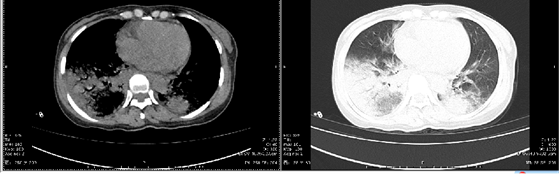

入院检查CT显示“双肺散在片状、大片状密度增高灶及模糊影,内见含气支气管影,右侧胸腔少许积液,心包少量积液”,临床表现为呼吸衰竭Ⅰ型、重症肺炎、低蛋白血症、电解质紊乱等症状。向开旺医生询问家属病史及查询外院检查单得知,马女士反复高热不退,血常规白细胞及血小板正常,淋巴细胞下降,常规病原微生物检测未见异常,在二级医院已使用3天高档抗生素,并未好转,且一直未查明病因。

胸片显示双肺大片渗出病灶